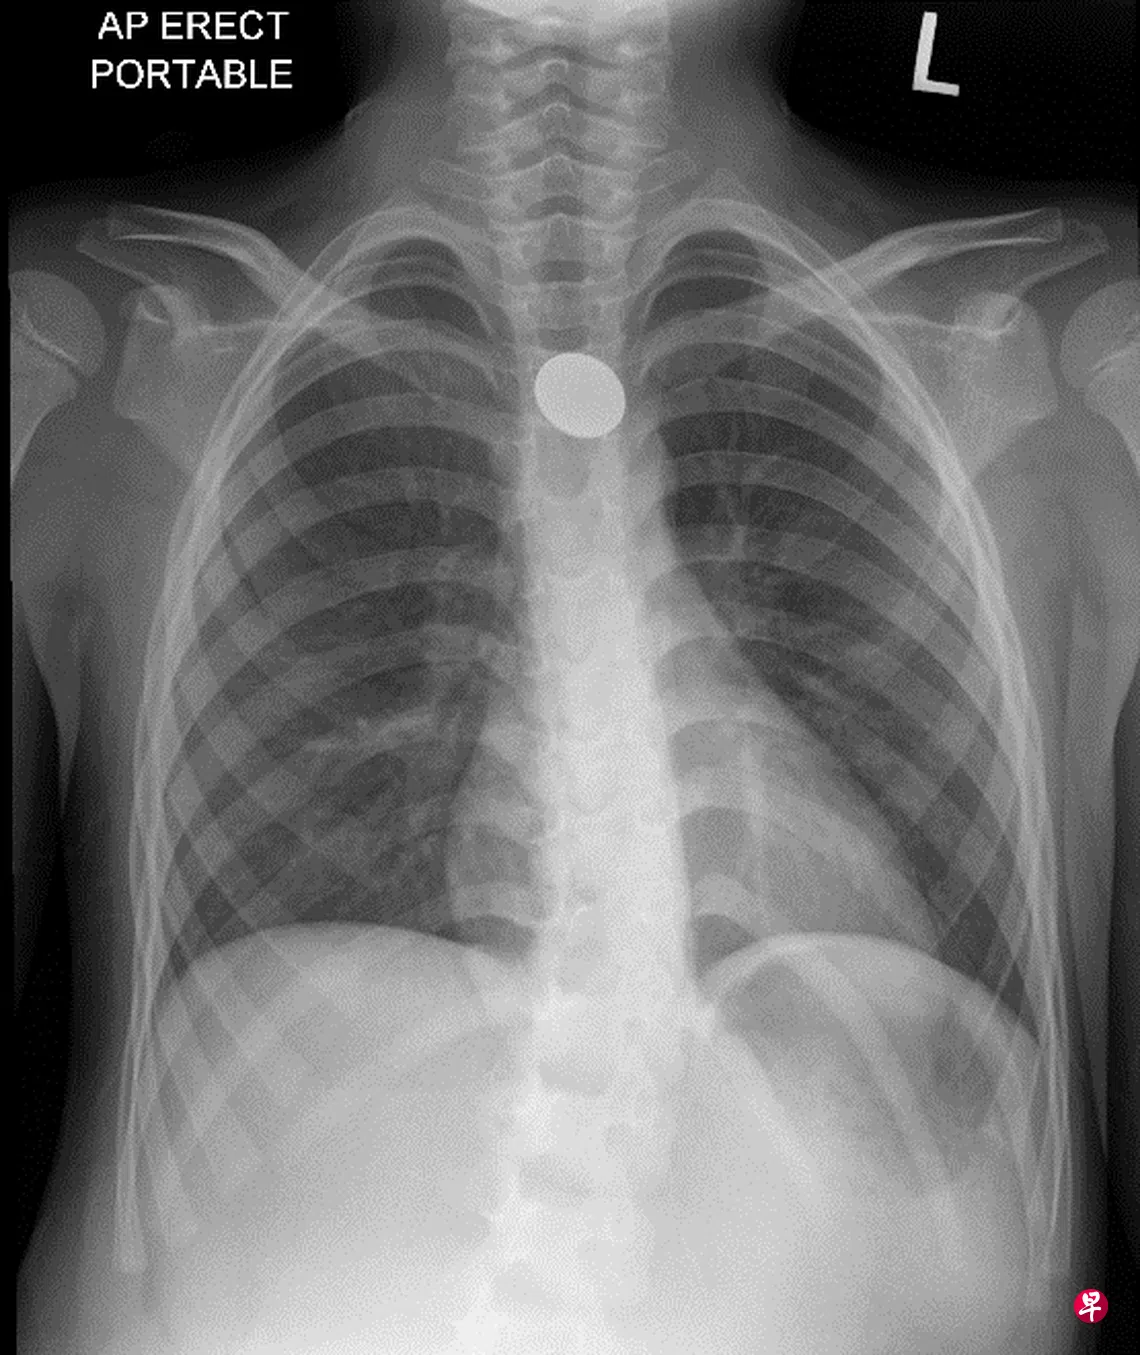

研究结果显示,硬币是最常见的误吞物,占41%,其次是玩具(27%)。超过80%的异物在14天内排出体外,最长的则需要37天(硬币)。根据研究,电池最多七天排出体外,其他不透射线(radiopaque)的异物,最长要23天。

异物可分为低风险(硬币、珠子或弹珠)和高风险(电池、多个磁铁或尖锐物体)两组,这个分类取决于吞下异物后可导致的潜在并发症。